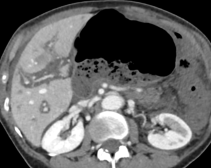

Module 1: Liver and biliary tract

Module coordinators : Prof. Christophe Aubé and Prof. Anita Paisant

Non-cirrhotic hepatic dysmorphia- Hepatic steatosis – advanced level

- Other hepatic storage diseases (beyond steatosis)

- Vascular liver diseases - clinical cases – advanced level

- Benign liver tumors – advanced level

- Rare liver tumors

- Hepatic pseudotumors

- Cholangiocarcinoma – advanced level

- Liver metastases – advanced level

- Hepatic capsule diseases

- Post–liver transplantation imaging findings

- How to use hepatospecific contrast agents – advanced level

- Contrast-enhanced liver ultrasound

- Ultrasound elastography

- MRI elastography

- Role of spectral CT in hepatobiliary diseases

- Indications for PET-MRI in abdominal diseases